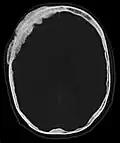

Scanner d'une métastase ostéocondensante dans l'os du crâne d'un patient souffrant d'un carcinome de la prostate. On reconnaît clairement l'extension de la métastase au-delà des limites initiales de l’os.

Par comparaison, scanner de métastases ostéolytiques dans l'os du crâne d'une patiente souffrant d'un cancer du sein. On distingue une ostéolyse plus grande sur le front, et plusieurs plus petites.